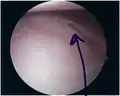

Bankart lesion

The glenoid labrum, labeled glenoid ligament, is damaged in a Bankart lesion. Lateral view demonstrating the articular surface of the right scapula is shown.